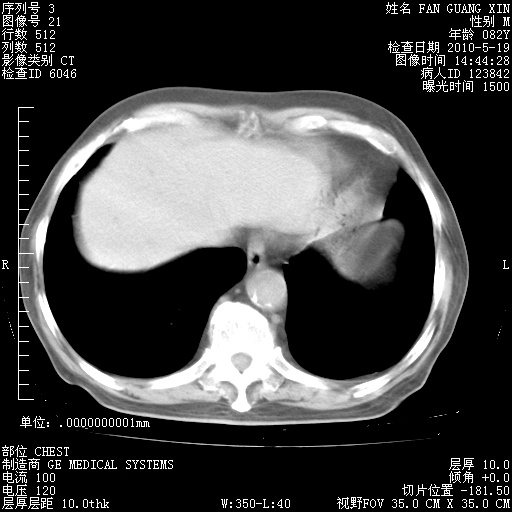

治疗3周后的肺部CT纵隔窗

再治疗10天后的肺部CT

再治疗10天后的肺部CT 纵膈窗

阅读此次胸部CT,肺间质渗出性改变较入院时有吸收。目前从体温、白细胞、中性分叶明显增高,肯定存在细菌感染(发生医院感染哦,若无消化道及泌尿系统等感染的依据,肺部感染可能大)。若你院头孢哌酮舒巴坦钠耐药率较高,同意你的方案,若48小时体温仍高,可考虑使用碳青霉稀类抗菌药物,同时可予超声雾化、注意滴数时加大液体量。白蛋白33.30g/L较低哦,需加强营养等支持治疗。